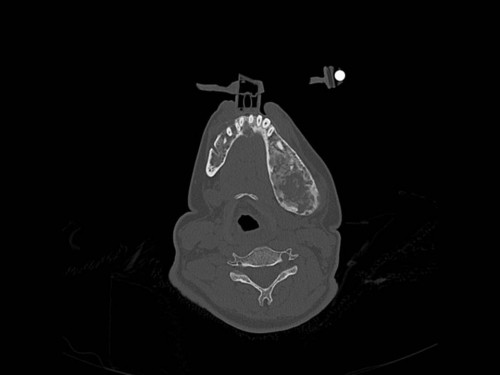

Eine 16-jährige Patientin kommt in eine MKG-chirurgische Praxis zur Abklärung der weiteren Vorgehensweise bzgl. ihrer Erkrankung.

Sie betrachten die angefertigten Röntgenbilder. Welche der folgenden Röntgenbefunde ist korrekt? Ossäre Auftreibungen im Bereich …

- A… der Mandibula links.

- B… des Os frontale links.

- C… des Os zygomaticum links.

- D… des Os temporale links.

- EAlle genannten Aussagen sind korrekt.

Bildgebung - OPAN 2004